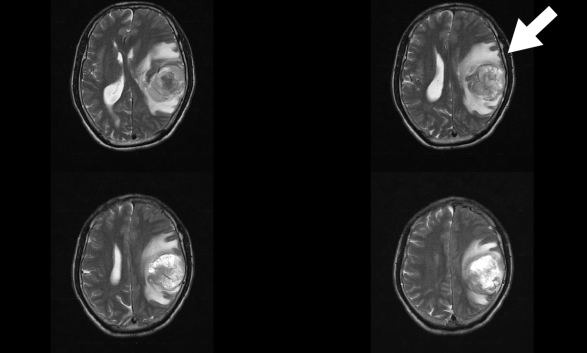

陳先生早晨起床時,突然感覺肢體無力,言語不清,站立、持物等活動受限。他被緊急送到醫(yī)院,急診ct檢查發(fā)現(xiàn)左側(cè)顳頂葉腦出血,并且疑似腫瘤出血。醫(yī)生進一步檢查發(fā)現(xiàn),患者顱內(nèi)巨大腫瘤并卒中(出血),情況十分危險,緊急開通綠色通道施行手術(shù)才保住了生命,病理診斷是膠質(zhì)瘤!